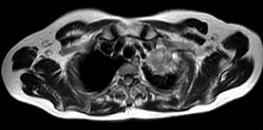

- 单项选择题男,68岁, 声音嘶哑半月,行MRI检查如图, 其最可能的诊断为 ( )

A、右上肺癌

B、左上肺结核球

C、左上肺炎性假瘤

D、左上肺癌

E、左上肺动静脉瘤